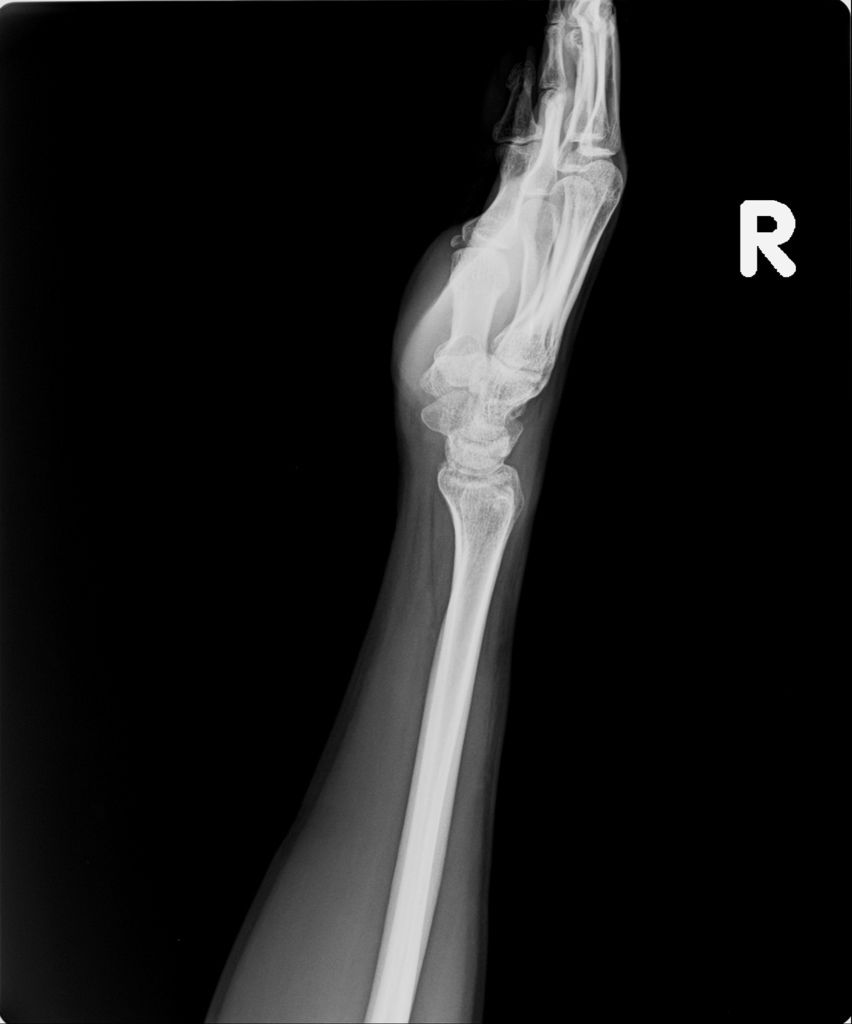

右手X光↓

請他騎在我的後面。 小純跟賣水果的人,都建議我不要騎車, 但我還是執意要騎。我再度站了起來, 發現我還是無法站穩, 忍痛坐上機車之後, 發現右手也不太能催油門,

只能小小力的發動。 辛苦的騎到加油站加油之後並騎回家。

之後幾天,就是充足的休息了,手腳都骨裂,我原本以為腳裂會對我的生活比較麻煩,因為行動不便。但後來發現,真正影響我生活的,是手。因為打上石膏之後,還是能夠走到目的地,只是走的比較慢而已,在家裡頭其實也不用走很遠。但手就不一樣了,骨裂的是慣用手右手,手腕不太能轉,做許多事都受到限制,從原本的右主左輔,變成了左主右手卻不太能輔助,這幾天真的是幸好有小純的照顧,否則不知道該如何是好。

手沒什麼進展這件事,讓我比較吃驚,詢問黃醫師,手如果也改用副木,會不會比較好,黃醫師說,他個人是認為沒什麼差。他看著X光片照出來的結果,說開刀或不開刀他覺得都差不多。

離開門診後,我跟媽討論了一下,我說我的手明明能動的範圍變大了,怎會沒什麼進展?媽說有可能之前會痛是因為發炎的關係,和骨頭無關,現在發炎好了,手就不那麼痛了,我聽了感覺蠻有道理的,只能等骨頭慢慢癒合了。